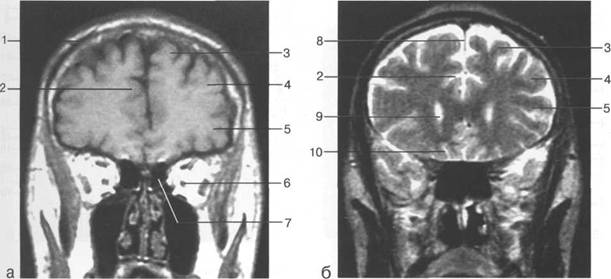

Задняя череп 13513u2010n 85;ая ямка представляет собой часть основания череп 13513u2010n 72;, ограниченную централь

Следует отметить, что в настоящее время оптимальным методом исследования структур задней череп 13513u2010n 85;ой ямки является МРТ, которая, в отличие от КТ, лишена артефактов от кост

Мозжечок заполняет практически весь объем задней череп 13513u2010n 85;ой ямки. Его поперечный раз

IV IV IV IV III IV

височная доля; 17 - полушарие мозжечка; 18 - |